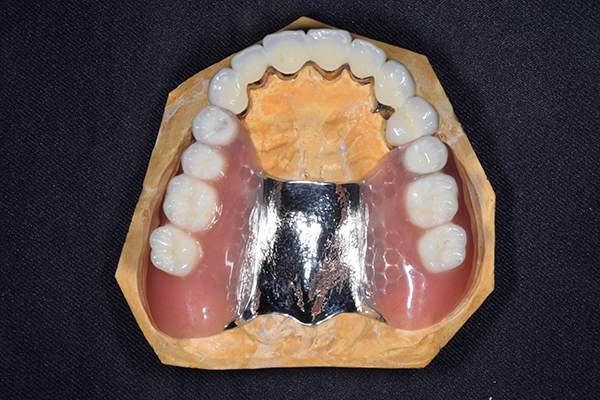

ケース3(インプラントを用いた部分入れ歯)

右上と左下の歯がない方です。 上の入れ歯の安定が悪く、作り直したいとのことでいらっしゃいました。 今お使いの上の入れ歯を見てみると、口蓋部分が抜けており、安定性に欠ける構造になっていました。この入れ歯はノンメタルクラスプデンチャーといって、金属のバネを使用しない 入れ歯になります。これは見た目は良いのですが、歯への負担が大きいことと、入れ歯自体がやわらかいため、噛むには不便なことがあります。

入れ歯は極力薄くするために金属を使用しました。しっかり噛める様にするため、ノンメタルクラスプデンチャーにはしませんでした。

上の入れ歯(表)

上の入れ歯(裏)

下の入れ歯